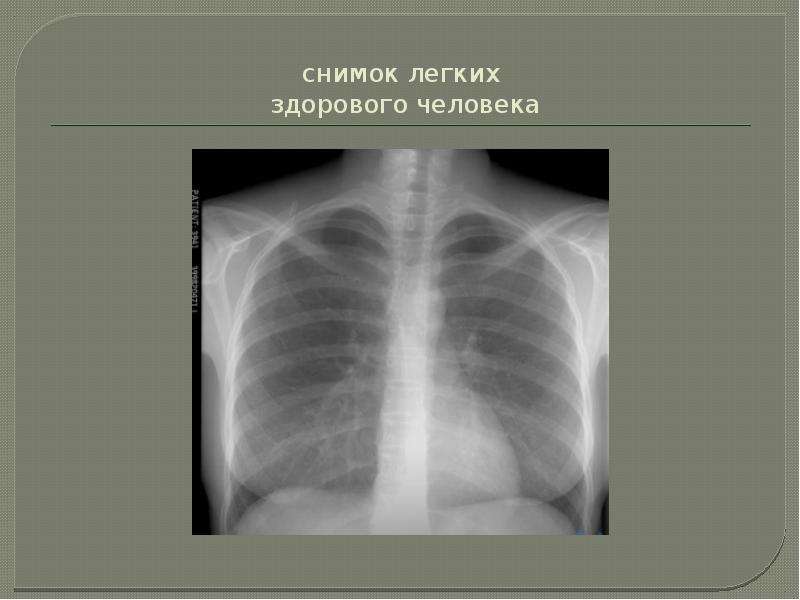

Нормальная рентгенограмма легких: что нужно знать

Раздел: Мудрость в объективе